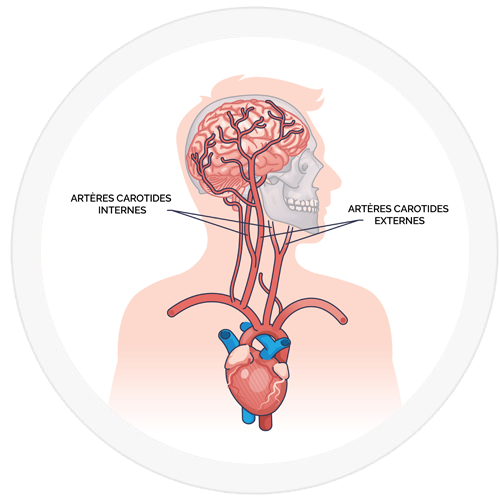

TRONCS SUPRA-AORTIQUES – ARTÈRES ETUDIÉES

Les artères étudiées lors de cet examen sont :

- Artères sous-clavières depuis la base du cou jusqu’aux épaules

- Artères carotides depuis la base du cou jusqu’à la base du crâne :

- Carotides communes

- Carotides internes

- Carotides externes

- Artères vertébrales